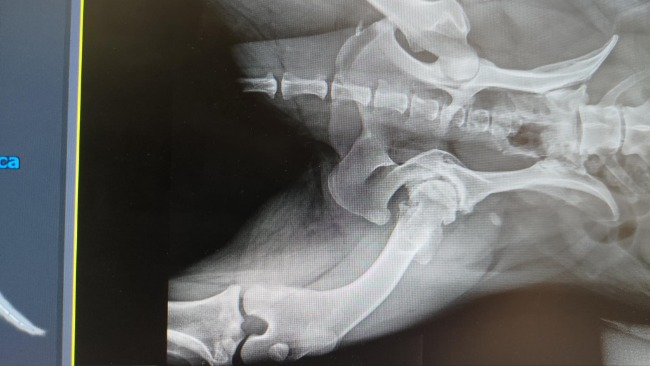

Zdjęcie RTG z 2020 roku:

Obecnie odbyłyśmy z Misią kolejną konsultację, której konkluzja jest jednogłośna - należy dokonać resekcji głowy kości udowej. Staw Misi jest na takim etapie uszkodzenia, że ani endoproteza ani leczenie komórkami macierzystymi nie są możliwe.

Zdjęcia RTG z bieżącego roku:

Jak widać Misia nie może do nich nawet wyprostować łapy :(